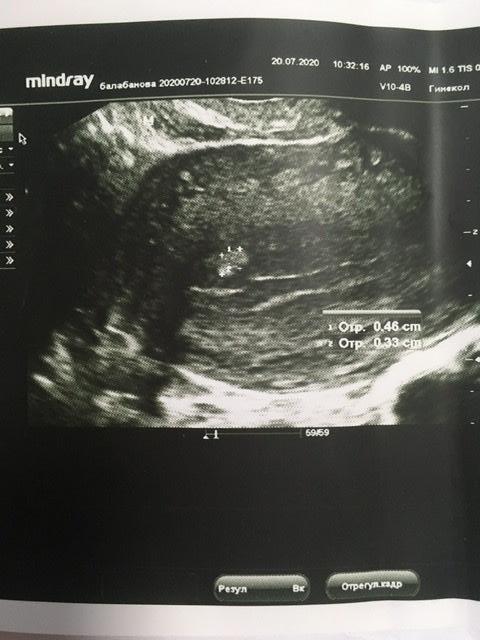

Девочки, у кого были полипы эндометрия , небольшие , у меня 3/4мм .может полип быть без ножки ? или это может быть что-то другое, аномалия эндометрия какая-то . Откликнитесь , у кого какие были , и возможно кто-то знает причину появления полипа в матке .

У меня был , образовался после приема клостилбегита , давно , удалили в 2016 , в прошлом цикле стимулировались без таких препаратов , просто укол овитреля , разве может быть от него? Это же хгч (

Большой полип был? Сколько мм , не помните?